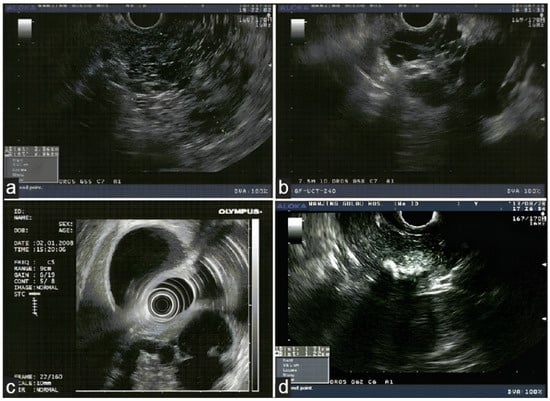

3. Conventional (Radial and Linear) Endoscopic Ultrasound

4. Miniature Probe Endoscopic Ultrasound